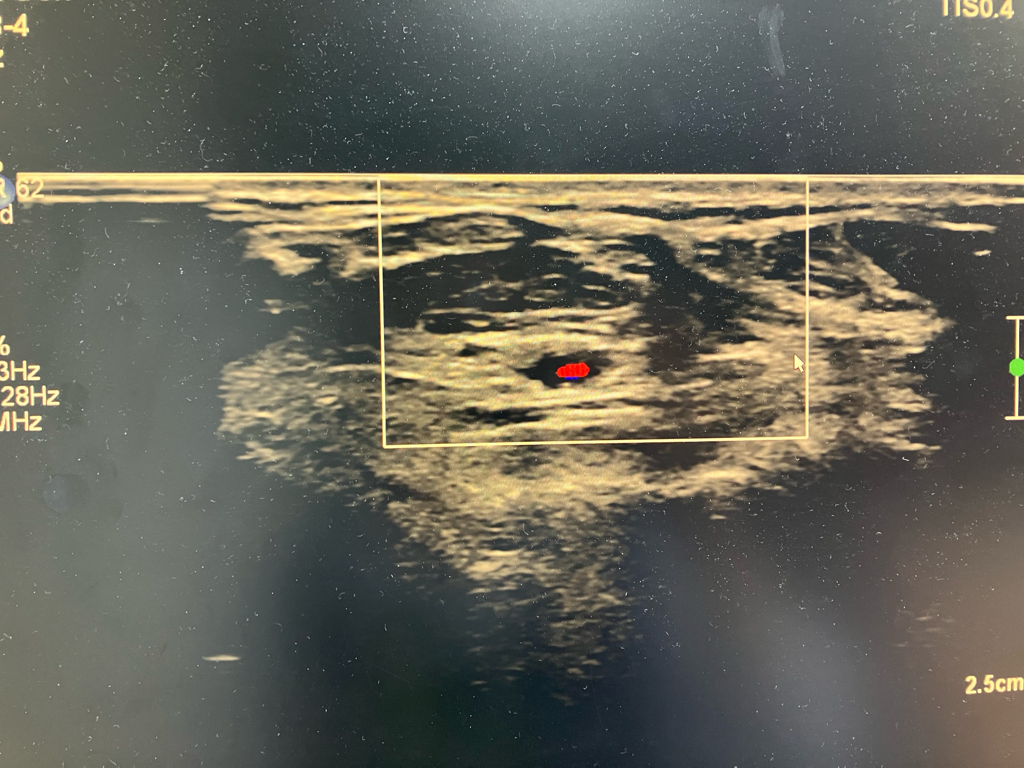

초음파는 이렇게 찍어놓은것만 보고 판단하기 어렵고 실시간으로 보면서 판단을 해야합니다.